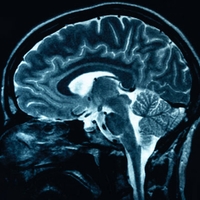

Хроническая депрессия вызывает атрофию головного мозга

Известно, что депрессия, постоянная тревога и прочие психологические расстройства медленно, но верно подтачивают мозг: хроническая депрессия, например, вызывает атрофию гиппокампа. Здоровье и функциональность нейронов зависят от нейротрофического фактора мозга (BDNF), и считается, что психологические расстройства снижают уровень этого белка, из-за чего нервныt клетки начинают себя плохо чувствовать и вообще голодать. Но, кроме BDNF, от психологического состояния зависит ещё и активность гена нейритина — менее изученного белка, про который известно, что он участвует в реорганизации синапсов.

Но, что более важно, само по себе повышение активности нейритина, безо всяких антидепрессантов, помогало справиться с последствиями депрессии. Если активность гена стимулировали, то никаких структурных изменений в мозге вроде атрофии нейронов и уменьшения синаптической пластичности, сопровождающих психологические расстройства, не было — даже в условиях сильного и постоянного стресса. И наоборот: если активность гена нейритина подавляли, то у грызунов проявлялись стрессовые и депрессивные симптомы, хотя никакому стрессу их не подвергали.

Иными словами, нейритин служит предохранителем, который защищает мозг от повреждений, спровоцированных стрессом. Но сильный стресс, в свою очередь, может блокировать работу нейритина. Вряд ли он такой один, но важность этого белка всё равно трудно переоценить.